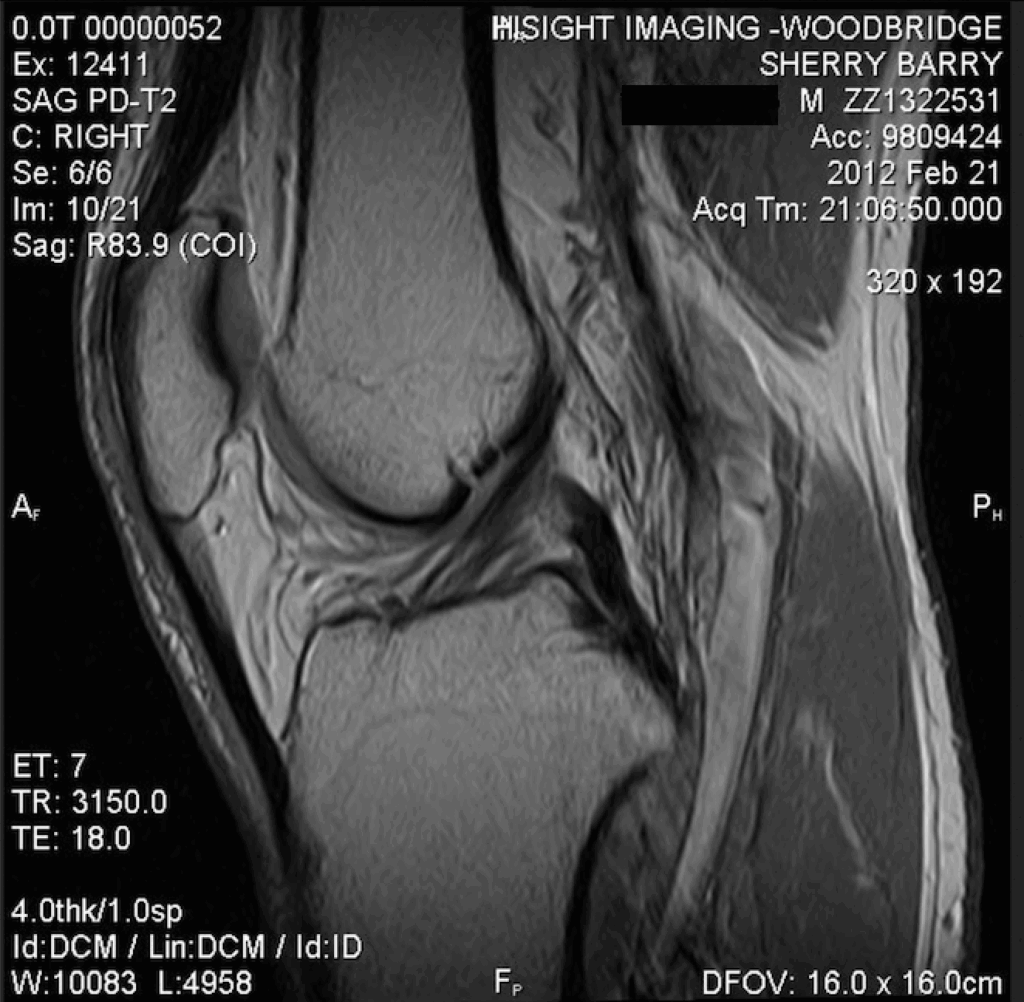

My knee has been hurting, especially when walking or running. I don’t remember suffering a traumatic injury – in fact, I don’t think there was one. But it was always worse after I played Ultimate (sometimes incorrectly called Ultimate Frisbee). Since there wasn’t an injury, I just have to think about how long this has been bothering me. Probably about 10 weeks.

My doctor did some range of motion tests and diagnosed it: A torn meniscus.

I had foot surgeries in 2003 and 2004. And a torn meniscus in 2006.